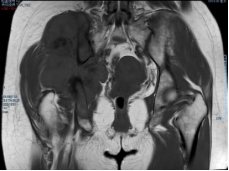

术前影像

术前截骨规划

3D打印假体设计

据主刀医师徐生林介绍,本例病例将整个右侧半骨盆Ⅰ+Ⅱ+Ⅲ+Ⅳ区(累及骶骨)进行整块切除,同时切除肿瘤覆盖的部分骶骨。3D打印假体所有骨接触界面均设计为骨整合结构,有利于骨长入和骨盆假体的永久稳定。耻、坐骨结构不规则,因此设计组配式结构,有利于术中操作,极大地方便了术中的假体安装。

3D打印技术的出现,使骨肿瘤的精准切除成为了可能,3D打印制造技术能够很好地适形匹配肿瘤切除后的骨结构,通过假体-骨接触面的特殊制造技术达到假体-骨整合,解决了骨肿瘤切除后大段骨关节缺损的重建问题,在生物力学重建和功能重建上比常规假体优势明显。3D打印假体使骨肿瘤切除重建进入“个性化、精准化、私人定制”时代。